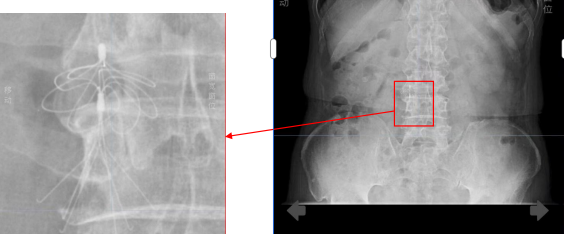

当时,因严重下肢静脉血栓,王大爷接受了下腔静脉滤器植入术,这枚金属滤器如同一张“血管防护网”,曾有效拦截血栓,守护了他的生命。可如今,它却成了房颤导管消融手术的“拦路虎”——该手术常规路径需经大腿股静脉,通过下腔静脉进入心脏,但滤器恰恰堵住了这条必经之路。若强行通过可能导致滤器移位、血管破裂或血栓脱落,风险极高。加上滤器植入时间过长,取出滤器的风险同样不亚于手术本身。

不过,为了降低手术风险,团队决定用上多种技术精准护航。一是依靠三维心腔内超声和三维电生理标测系统来导航,就像为手术装上了透视眼和GPS地图,能实时看清心脏结构,精准定位病灶。二是采用“零射线”技术,可避免X线辐射对患者,尤其是对老年患者、孕妇幼儿的潜在影响。

经过对影像资料反复推演,团队终于为王大爷量身定制了创新方案:经右侧颈内静脉入路,在三维超声引导下实施零射线房颤射频消融术。

手术当天,在轻柔音乐的舒缓下,陈雄彪团队开始了这场精细操作。首先,他在王大爷右侧颈部完成毫米级精准穿刺,将导管经上腔静脉送入右心房。

随后,手术最关键的一步——房间隔穿刺开始了,他在无X线透视的情况下,仅凭三维超声影像,将导管安全穿过心房之间的墙壁,进入左心房,每一步都需极度谨慎,“就像在黑暗中仅凭手感与地图穿越迷宫。”陈雄彪说。

导管到位后,标测系统开始绘制精细的心脏电路图,捕捉异常电信号;消融导管则对紊乱的“起火点”——通常位于肺静脉口部进行精准隔离。时间一分一秒过去,手术室内团队全神贯注。

历经约4小时,三维系统显示:两侧肺静脉电位完全消失,异常电传导被彻底阻断——这意味着房颤的“根源”已被成功隔离,手术成功了。